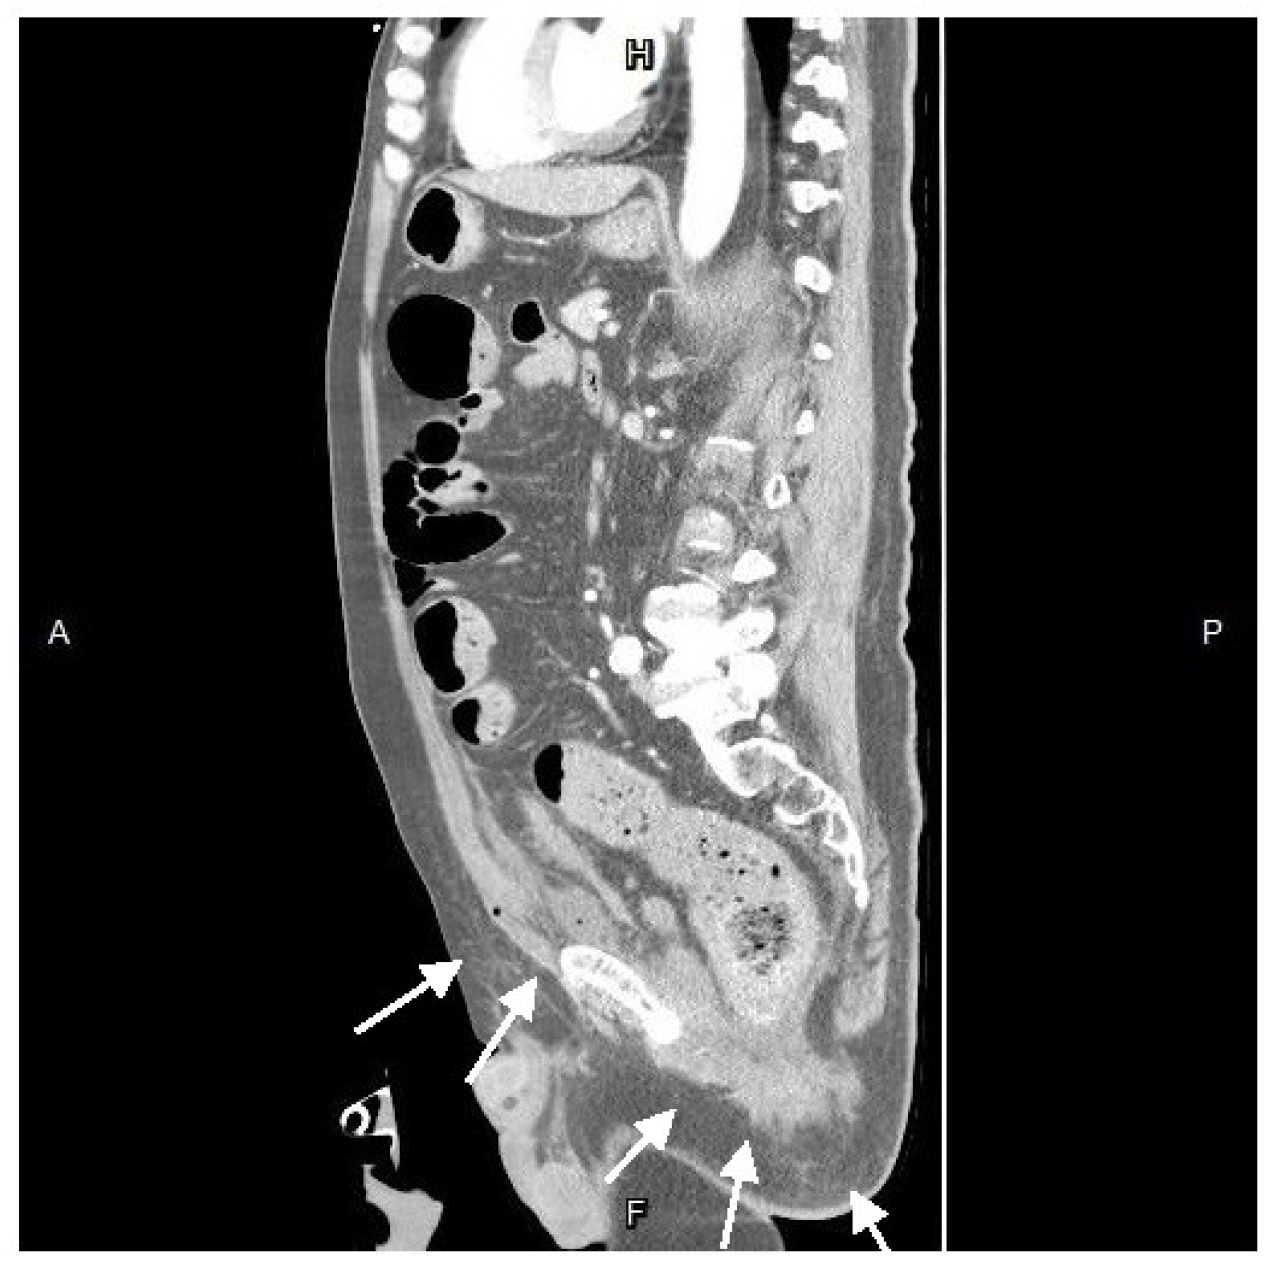

After resuscitation and blood transfusion, his vital signs stabilized, and the inotrope was tapered. Upon the next day, we consulted a radiologist for CT-guided extraperitoneal abscess drainage, (Figure 4) collecting a considerable amount of turbid fluid. Cultures from the pus identified Klebsiella pneumoniae, Escherichia coli, Viridans streptococcus gr., and Bacteroides fragilis.

Figure 4. A computed tomography-guided percutaneous drainage(arrow) procedure.